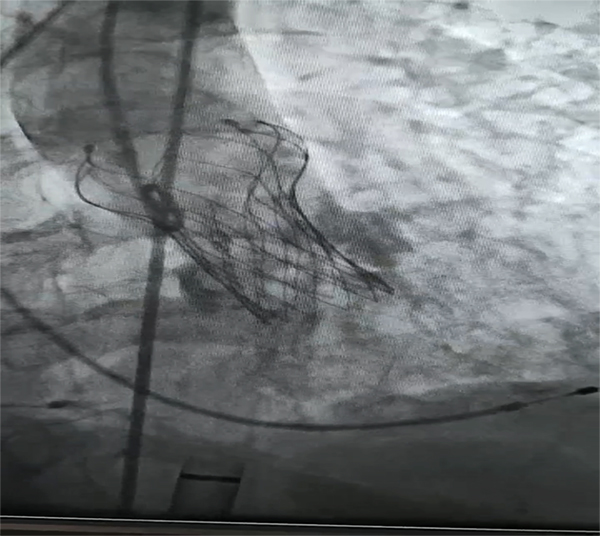

為保證手術順利進行,心血管內科負責人劉艷麗帶領科室團隊與其他相關科室MDT合作,進行術前討論,最終給患者選用VitaFlow Liberty全球唯一的電動可回收輸送系統,并行左冠脈保護。

21日上午,在多學科協作下,柳州市人民醫院心血管內科陳見紅、苗柳、王勇,麻醉科王小平,超聲科陳超容團隊經過2個小時緊張有序的操作,取得了TAVR手術圓滿成功,術后患者即刻清醒。